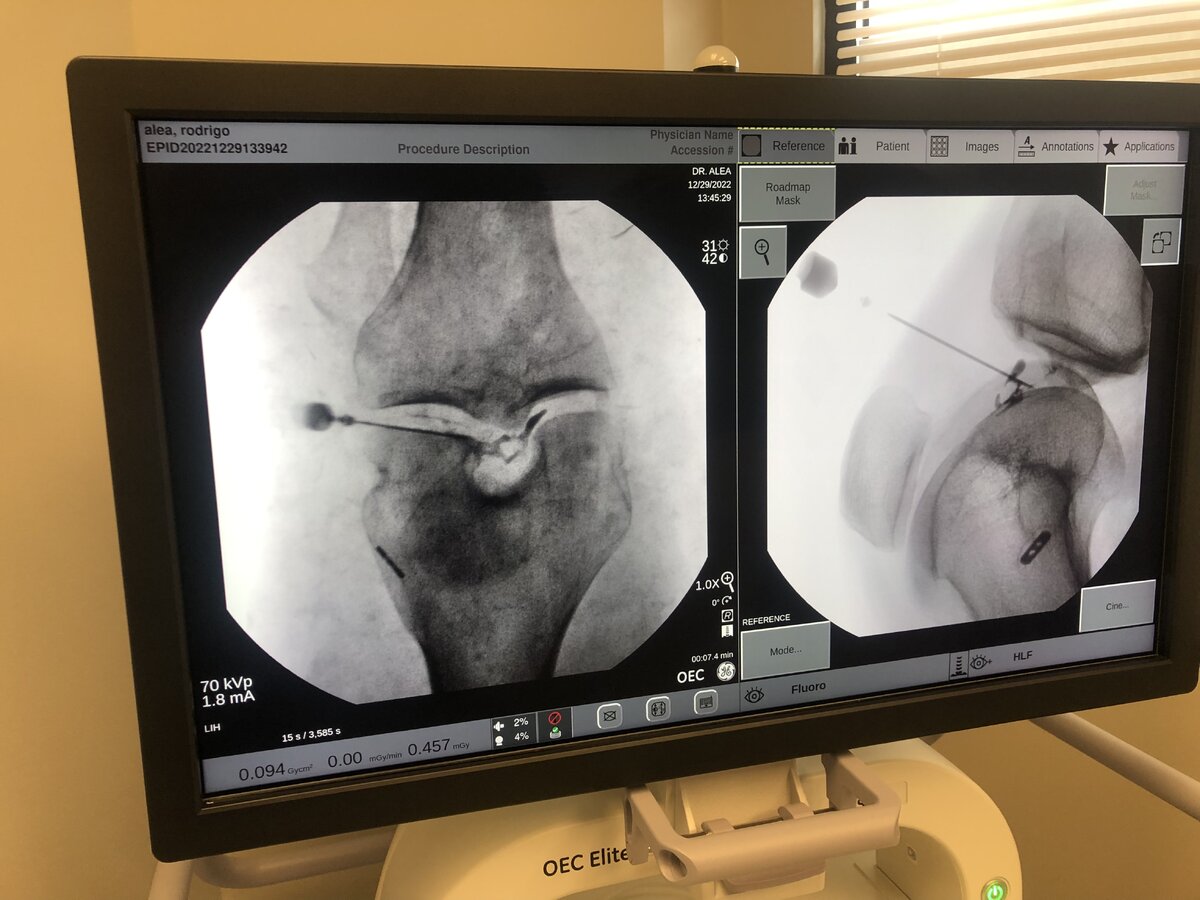

My 21 y/o brother blew out his knee and had total reconstruction last year. He has been stiff and walked with a limp ever since. Ortho said he scarred poorly when he was in there. Finally able to get him into office for PRP. Next day he said it hasn’t felt this good since before surgery.

73A03121-5718-4019-B2DA-A0782FE75388.png

0FF65EF9-3977-4DF2-9658-1790B03BB6A3.jpeg